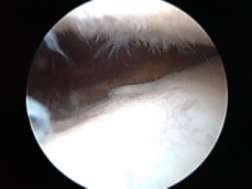

使用关节镜观察膝关节内部:

I度:探针可触及关节软骨软化,少量表面纤维化